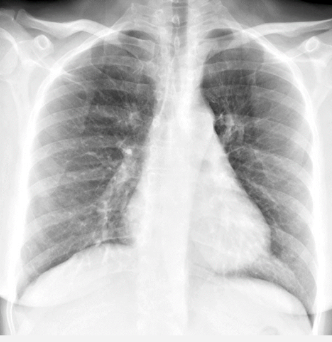

pulmonary HTN!!!! - r heart enlargement and dilated pulmonary arteries

Chronic disease:

- Dilation of right & left main and lobar pulmonary arteries

Advanced disease:

- Right ventricular & right atrial enlargement